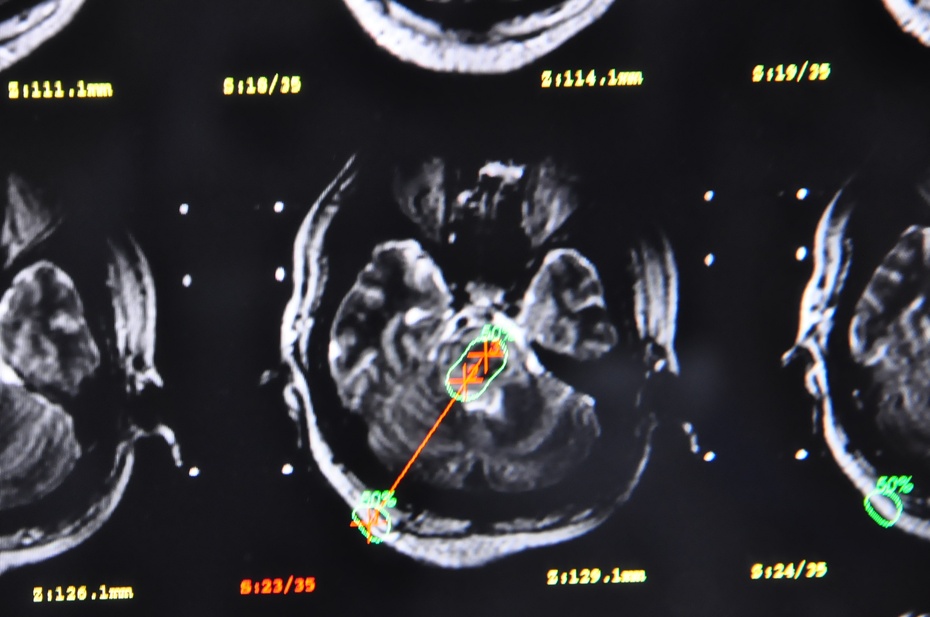

患者29岁急诊来院时已陷入深昏迷,血压达220/100mmHg,急查头颅CT见脑干内不仅已形成血肿,且出血仍有向桥脑下方和延髓方向继续侵袭倾向,患者随时有呼吸心跳停止的可能,病情十分危急。因送诊路上呕吐已经有误吸,紧急抢救,吸引出呕吐物才防止窒息死亡,并紧急降压、止血,稳定住了生命体征,为手术救治赢得了宝贵时间。在CT影像上到脑干中央有白亮的出血团影。右枕下仅切开2cm头皮小切口,钻开颅骨,从仅1cm直径的骨孔内用尖刀切开硬膜,电灼蛛网膜、避开横窦和皮层血管、确认小脑表面穿刺点……再次核对各项靶点数据后,闪亮的金属穿刺针从导向弓轻轻滑过,指向A点。

穿刺针轻推刺入,凭着手中细微感觉,进入小脑、穿过小脑、进入环池、进入脑干、到达血肿!整个手术室都屏住了呼吸…“麻醉注意心电监护!”进针精准地停止在零刻度靶心,拔出针芯、置管、抽吸,一股暗黑色的积血瞬间引出…